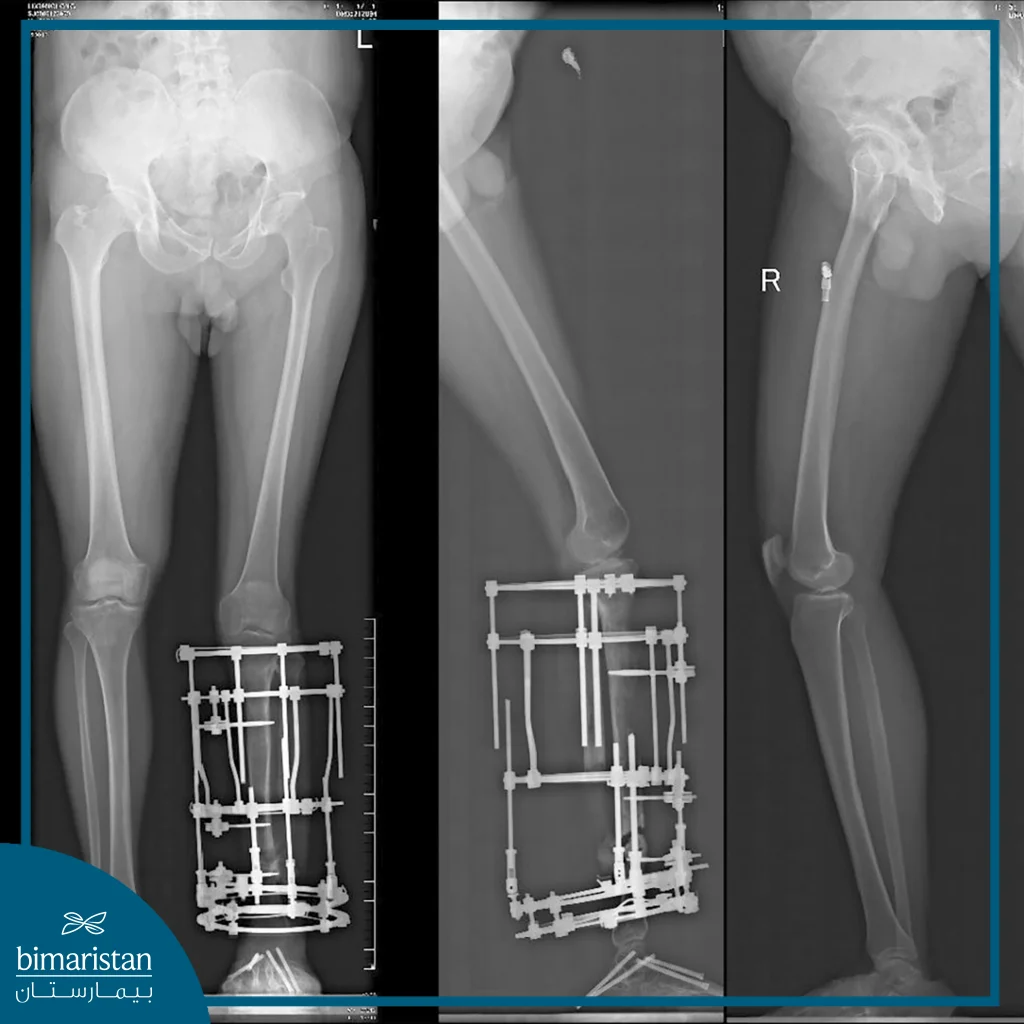

The Ilizarov operation is a surgical technique used to treat complex orthopedic issues, whether related to fractures or bone deformities, as it relies on the use of an external device that is fixed around the broken or deformed bone. The device is adjusted to adjust the position and length of the bone or to stabilize it appropriately, and the Ilizarov device is an advanced tool that provides flexible and effective solutions for many cases that are difficult to treat with traditional methods.

The Ilizarov operation is mainly used in the treatment of comminuted or complex fractures. It helps in lengthening bones and treating deformities resulting from injuries or chronic diseases such as osteoporosis. This technique contributes to the correction of congenital or acquired deformities such as curved legs and accelerates the healing process of delayed fractures. The Ilizarov device is the ideal solution for many cases that require great precision in handling and treating bones.

- Making the incision: In the next step, a small incision is made in the area of the fracture or bone deformity, the aim of this incision is to stabilize the bony limbs with a specific mechanism using metal screws and cylinders, so that the bones can gradually grow under the influence of the device, and the Ilizarov device consisting of metal rings and braces is placed on the bones to stimulate the lengthening or adjustment process.

- Bone stabilization using the device: After determining the location of the fracture or deformity, the Ilizarov device is fixed to the bone using strong metal wires, these wires are connected to other elements of the device to create a supportive structure that allows the bones to move gradually, this device allows the bones to be adjusted or lengthened depending on the needs of the case.

- Gradual bone lengthening: Once the device is in place, the slow lengthening of the bones begins, a process that requires extreme precision. The bones are gradually moved by a very small amount (usually 1 mm per day), allowing the bones to grow into the gaps created by the lengthening, during which time doctors monitor the progress of the process and supervise the bone healing process.